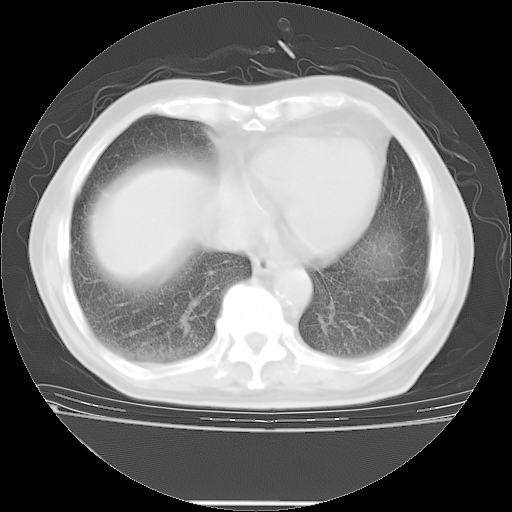

今天复查肺部CT,发现双肺广泛磨玻璃样改变。所以我把3月19日和5月9日相隔50天的肺部CT上传。请大家会诊。

2009年3月19日肺部CT片。

2009年3月19日肺部CT

5月9日肺部CT(在4月27日齐鲁医院肺部CT描述部分肺组织磨玻璃样改变,12天后肺组织广泛磨玻璃样改变)